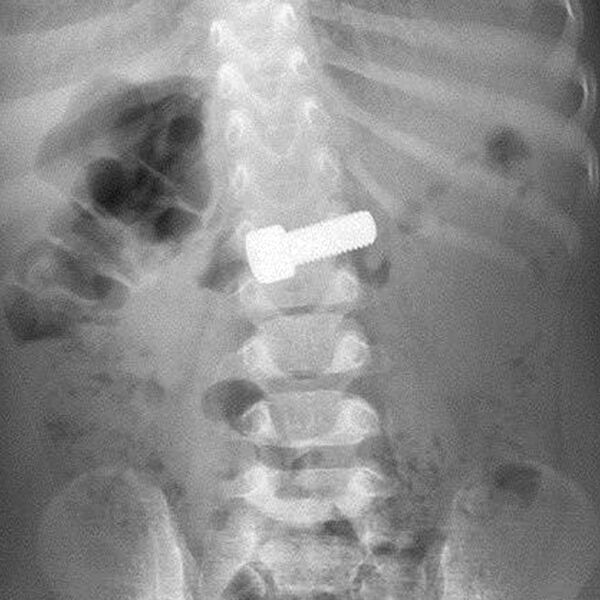

В Московской области врачи спасли годовалого ребенка, который случайно проглотил крупный металлический болт. Об этом сообщает Минздрав региона.

Годовалый ребенок играл и случайно проглотил болт, родители сразу вызвали скорую помощь. В приемном отделении ребенку сделали рентген, который подтвердил нахождение инородного тела в желудке. Врачи-эндоскописты оперативно провели процедуру по извлечению предмета с помощью специальной петли, которая заняла около 15 минут.

По словам медиков, благодаря быстрой реакции родителей, болт не успел причинить серьезного вреда. В противном случае инородное тело могло привести к непроходимости или повреждению стенок желудочно-кишечного тракта. Состояние маленького пациента оценивается как стабильное.